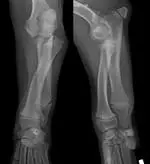

OutcomeAt a follow-up appointment 4 weeks after fixator removal, the puppy remained slightly lame in the left forelimb but showed subjective improvement from thepreoperative level of discomfort. The diminished range of motion remained unchanged. Still evident were antebrachial valgus and external torsion; it was noted that these issues may need to be surgically addressed in the future. Radiographs confirmed maintenance of reduction of the radial head but also showed remodeling and osteoarthritis (Figure 5).

Featured Image

Figure 5: Orthogonal radiographs of the affected antebrachium 4 weeks after removal of the external fixator. Note remodeling of the radial head despite the maintenance of its reduced positioning. Also noteworthy are the persistent angulation and torsion, which this technique does not address.